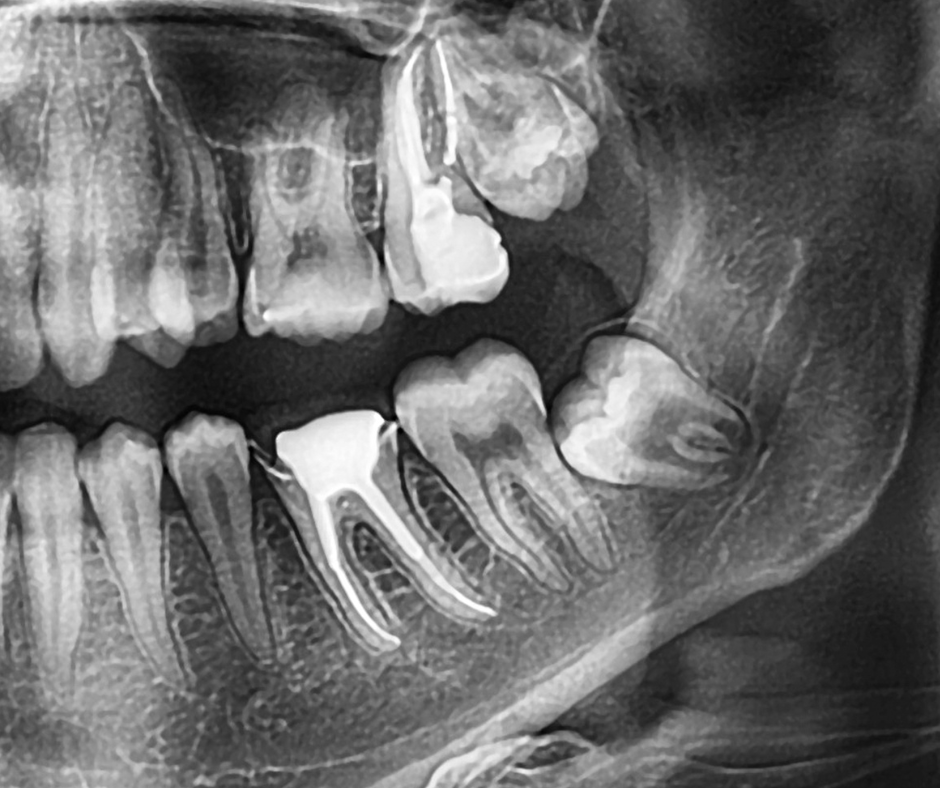

• Неправильное положение зуба. Он может расти под углом, упираясь в соседний зуб и разрушая его корень.

• Киста или воспаление корня. Иногда зуб мудрости остаётся в кости, не прорезывается и образует очаг инфекции, который видно только на снимке.

Иногда зуб не вызывает боли, но на снимке видно, что он расположен неправильно или оказывает давление на соседний. В этом случае врач может рекомендовать удаление профилактически, чтобы избежать будущих осложнений.

Удалять зуб мудрости или нет — решение, которое принимает стоматолог после осмотра и снимка. Если зуб растёт ровно и не мешает — его можно оставить. Но если он расположен неправильно, разрушен или вызывает воспаление, удаление — лучший способ сохранить здоровье остальных зубов.